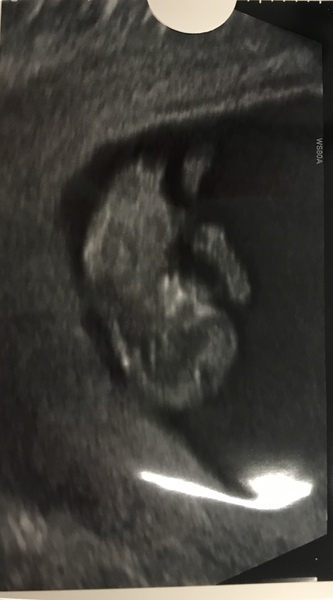

As expected, slightly too early for the nuchal measurement so I’m back for another scan in 2 weeks. Measuring as 10+6, EDD is 4th september but that can change. One bouncy little baby, exactly like its big sister!

Feels so weird to see an actual baby on the screen. I’ve felt so terrible that I haven’t really let myself think about it as a baby.